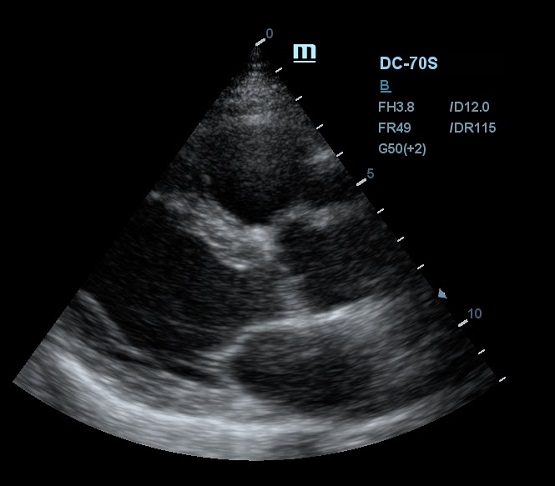

Благодаря постоянным инновациям, компания Mindray внедрила технологию iClear (адаптивная обработка изображений). Спекл - артефакт визуализации в виде акустического пятна - был препятствием для дифференциации структуры исследуемой ткани. iClear реализует агрессивное подавление спекл-паттернов, позволяя четко визуализировать анатомическую структуру на ультразвуковых изображениях. За счет уменьшения спекл-шума достигается лучшая дифференцировка тканей. Повышается контрастное разрешение без ущерба для пространственного разрешения. Уровень подавления спеклов можно выбрать под свои задачи, достаточно нажать кнопку или повернуть ручку, остальное сделает программный алгоритм.

Другим важным нововведением в постобработке ультразвукового изображения является система EchoBoost. Ткани миокарда отражают различные по интенсивности ультразвуковые волны, и при обработке их одним потоком качество изображение оставляет желать лучшего. Технология EchoBoost позволяет прибору производить анализ эхо-сигналов разной интенсивности индивидуально, создавая затем четкую картинку.